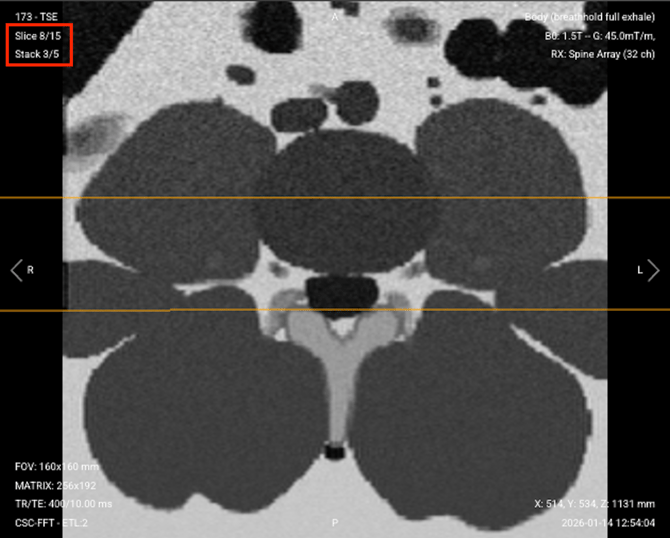

Resulting multi-stack acquisition. When you inspect the images you can see the progression of the slice number within the stack number of interest